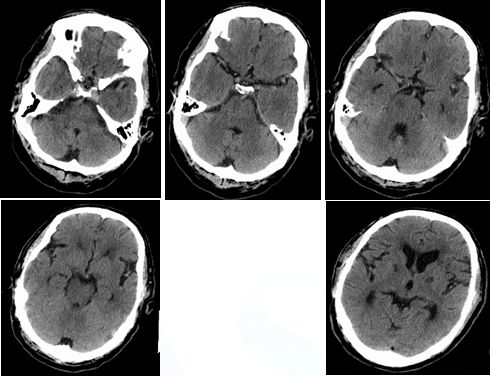

17:20颅脑CT排除出血

入院时颅脑CT(3.19)小脑梗塞

术后复查颅脑CT